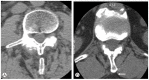

Methods: All patients were included in the study that underwent a decompressive procedure through spinous process osteotomy be between January 1, 2007 and December 31, 2007. Operation protocols were reviewed. A computed tomography (CT) scan was performed to evaluate the union of the osteotomies of the spinous process. According to the CT-scans, patients were divided into three groups: "complete-union," "partial-union," and "non-union." Patients reported their clinical results through a self-administered questionnaire.

Results: The mean period of follow up was 21.6 months (range, 16-28 months). A total of 44% of the performed osteotomies were considered as united. Ten patients (18%) were classified as "complete-union," 30 patients (55%) as "partial-union," and 15 patients (27%) as "non-union." The "complete-union" group showed better clinical results and scored significantly better in the Oswestry Disability Index and EQ-5D. However, no statistical difference was found in the pain-scores. There were no differences between the "partial-union" group and the "no-union" group.

Conclusions: We found a radiologic union for 60 out of 135 (44%) spinous process osteotomies.